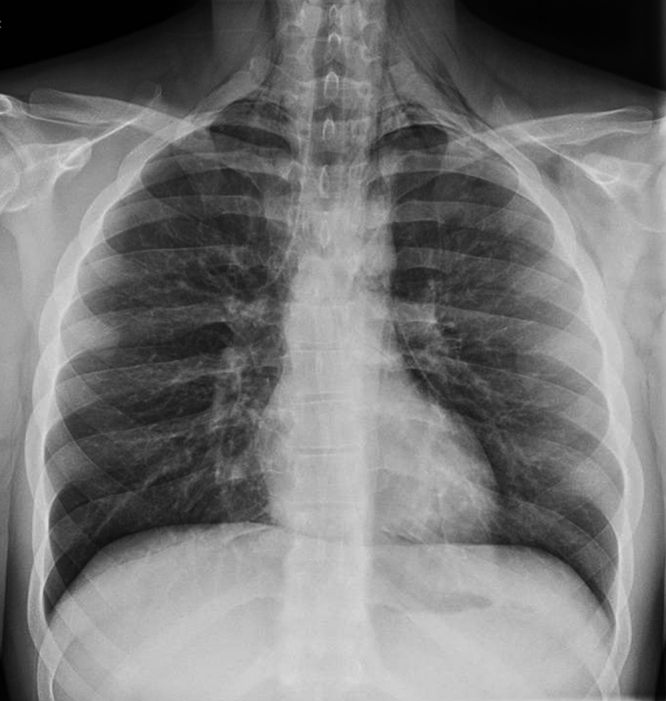

In view of the clinical signs, he was referred to the hospital accident and emergency service for an X-ray evaluation. A postero-anterior and lateral X-ray was carried out, in which air in the mediastinic area could be seen (Figures 1 and 2). A CAT scan was then carried out, which confirmed the presence of subcutaneous emphysema and air in the area of the mediastinum, with a clinical confirmation of spontaneous pneumomediastinum.

Figura 1. Pneumomediastinum in posteroanterior chest X-ray.

The clinical form of presentation is usually sudden chest pain, and dyspnoea of variable intensity; there may be difficulty or pain in swallowing, a crackling sensation when swallowing and changes in the voice2. The determining factors in the clinical examination are usually the presence of a subcutaneous emphysema in the neck and supraclavicular area, along with auscultation in the apex of a crackling that synchronises with the heart beat (Hamman’s crunch). A chest X-ray is important and necessary, always, as shall be shown, in the posteroanterior projection, the lateral displacement of the mediastinal pleura, which shall run parallel to the mediastinal vascular structures and the cardiac silhouette; in the lateral projection, air can be seen near the pulmonary artery and in the retrosternal area. Respiratory or haemodynamic functions are not usually severely compromised, and no specific treatment is required, apart from clinical observation until the symptoms and radiological alterations are resolved1. By doing so, a differential diagnosis can be established with a spontaneous pneumothorax, which does require specific treatment5.